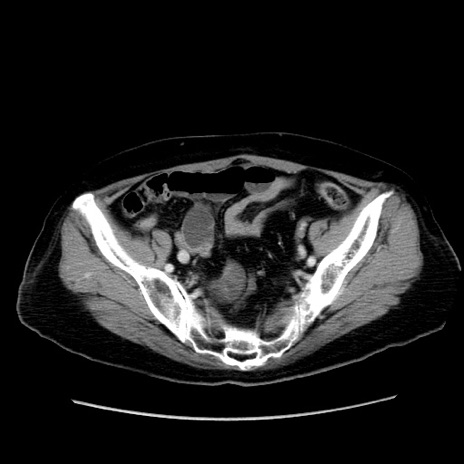

冠状断像

【症例】80歳代女性

【主訴】下腹部痛

【現病歴】約8時間前より下腹部痛の出現あり、救急外来受診。

【既往歴】両側付属器切除

【身体所見】意識清明、下腹部正中に手術痕あり、その部位に一致して圧痛と反跳痛あり。腸蠕動音は亢進。

【データ】WBC 9300、CRP 0.15